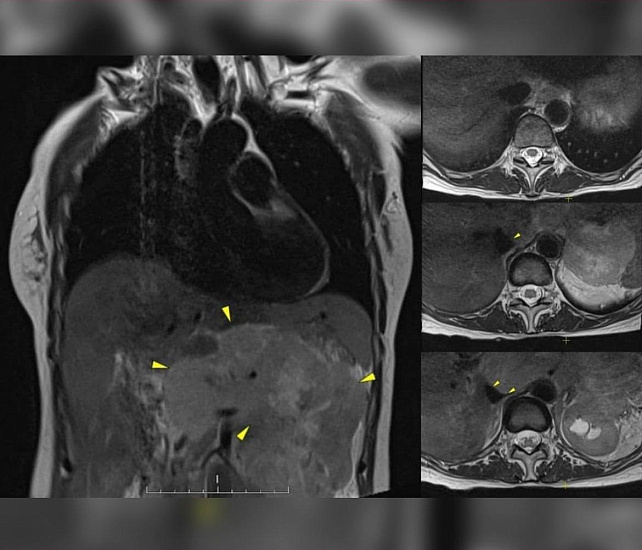

Диагностика показала наличие метастатических процессов с первичным очагом в грудной клетке. Это образование и было причиной болей. Результаты биопсии подтвердили лейомиосаркому.